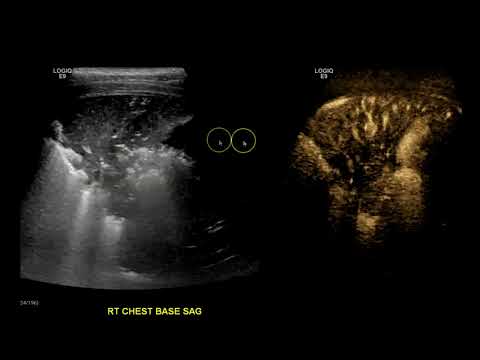

HomeResourcesProducts tagged “Pleural Effusion” Pleural Effusion Filter Showing all 5 results Default Sorting Sort by popularity Sort by latest Sort by editor review Added to wishlistRemoved from wishlist 0 Consolidation vs Pleural Effusion View + Added to wishlistRemoved from wishlist 0 How To: Ultrasound Detection of Pleural Fluid Case Study Video View + Added to wishlistRemoved from wishlist 0 Lung Ultrasound Normal Vs Pleural Effusion Image Appearances | Thoracic Spine Quad & Sinusoid Signs View + Added to wishlistRemoved from wishlist 0 Pleural effusion on ultrasound seen from different scan planes POCUS by Dr. Koratala (@NephroP) View + Added to wishlistRemoved from wishlist 0 Pleural effusion on ultrasound: the spine sign View +